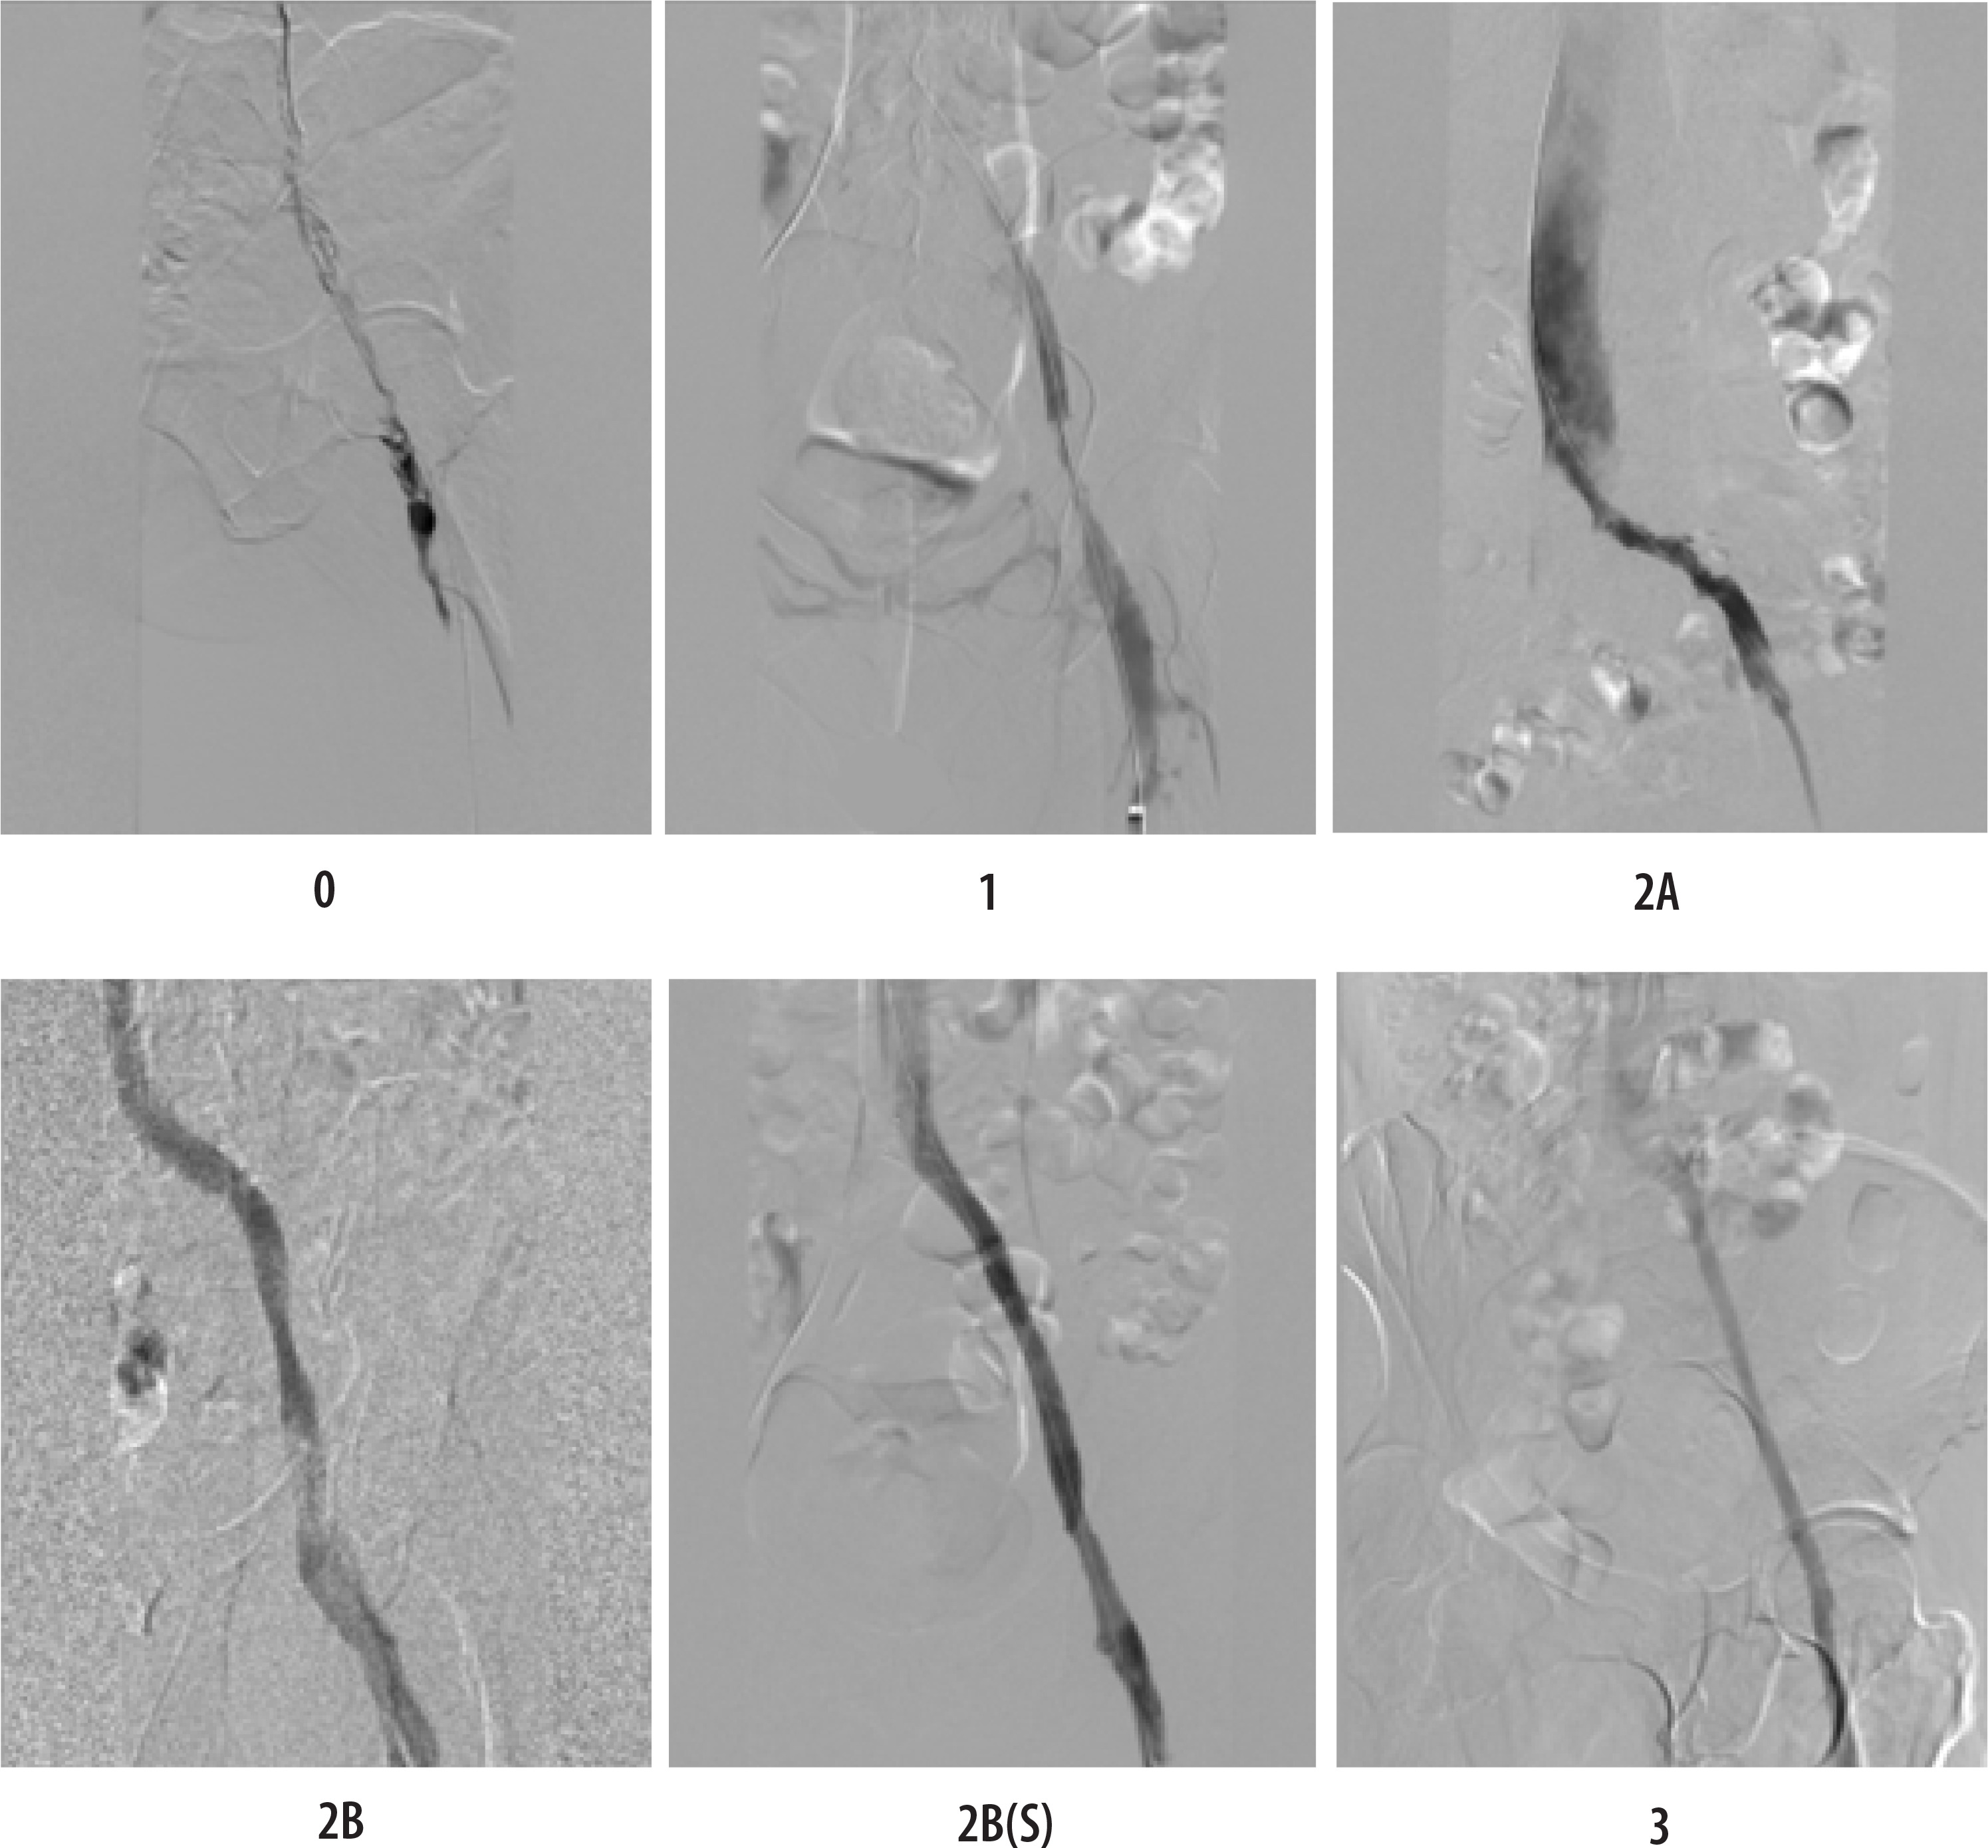

Figure 1

Representative angiographic images illustrating each grade of the proposed recanalisation scale

Grade 0: no recanalisation (completely occluded vessel);

Grade 1: partial recanalisation without spontaneous flow (flow only with compression);

Grade 2A: recanalisation with significant stenosis despite spontaneous flow;

Grade 2B: recanalisation without significant residual stenosis with spontaneous flow;

Grade 3: complete recanalisation with normal spontaneous flow and no residual thrombus or stenosis.

An optional “(S)” designation may be appended if stent implantation was used to enhance the angiographic outcome. Interobserver reliability was assessed using Cohen’s k statistic.